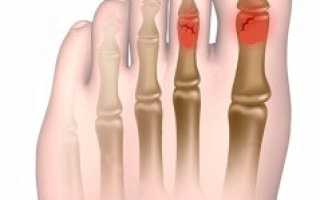

Перелом пальца на ноге – довольно распространенное явление, возникающее по двум причинам. Здоровые кости часто повреждаются в результате травмы (падения, удара, подворачивания стопы). Совсем небольшая часть (около 5%) переломов случается из-за нарушения прочности костной ткани одним из заболеваний – остеопороза, остеомиелита, туберкулеза.

Различают открытые (когда поврежден кожный покров) и закрытые переломы пальцев ног. Последние встречаются гораздо чаще. Есть немало способов, как узнать закрытый перелом. Однако, лучше это дело доверить врачу.

Когда костные отломки смещены, переломы могут быть:

• С угловым или боковым смещением. Встречается чаще в детском возрасте, когда надкостница отличается высокой эластичностью и риск ее повреждения минимален. Подобный вид перелома характеризуется смещением отломка кости в сторону. По этому признаку его легко отличить.

• С вклиниванием костных отломков. Хрящевая ткань при этом сильно деформируется. Часто образуются подсуставные трещины.

• С продольным расхождением отломков кости. Происходит тогда, когда повреждение мышц, связок повреждены в значительной степени.

• С продольным захождением. Подобные переломы встречаются часто. При сокращении мышц происходит стягивание окружающих тканей, благодаря чему отломки сдвигаются.

Линия разлома может находиться на любом участке фаланги пальца. Иногда повреждение случается одновременно на нескольких фалангах.